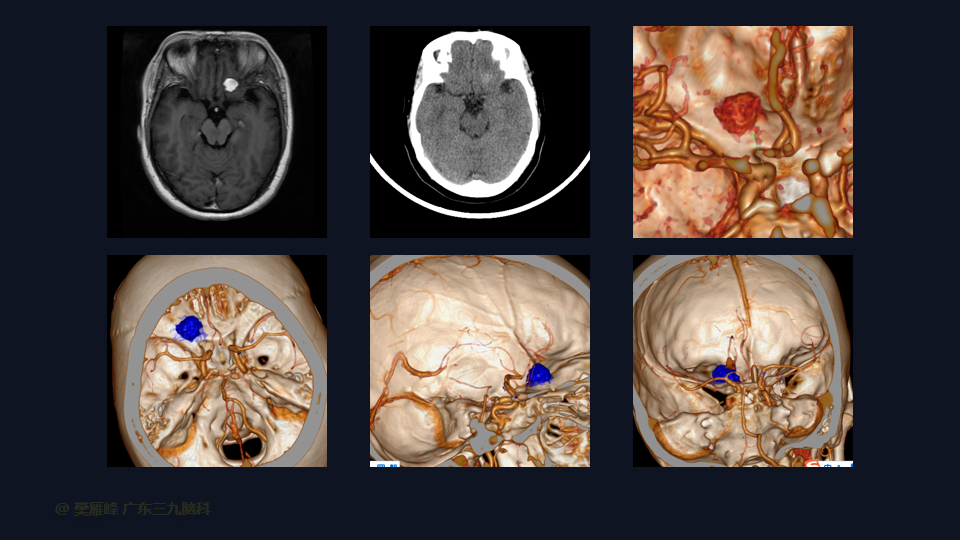

在这个二维手术视频中,展示了一种内镜经眶上锁孔入路微创切除嗅沟脑膜瘤的方法。患者是一名46岁的女性,有2年的头痛病史,近1周出现视物模糊,神经影像学显示左侧前颅窝底部示范围约12×16×10mm的均匀强化的嗅沟脑膜瘤。多种治疗方案被考虑,包括继续观察,开颅切除和内镜下经鼻切除。对于这种情况,内镜下经眶上锁孔切除是理想的治疗选择,因为这种方法避免了需要的脑牵拉,有更高的机会为 Simpson Grade I切除。他接受了内镜下经眉弓锁孔入路保护嗅神经的方法,以实现肿瘤全切除。术后无嗅觉障碍,视力较术前好转,神经影像学显示肿瘤全部切除。我们展示了安全的颅神经保护和内镜下肿瘤切除术的细微差别和技术要点,以及手术技术,以留下最少的残余粘附肿瘤。

在这段手术视频中,展示了一名46岁女性的病例,他因头痛1年余,加重伴视物模糊1周发现的前颅窝底嗅沟脑膜瘤